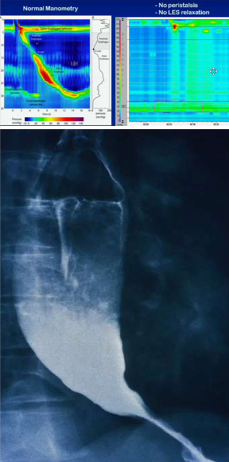

What would you expect to see on esophageal manometry in a patient with diffuse esophageal spasm? What about on barium swallow?

Peristalsis and contraction all at the same time. Barium swallow = corkscrew esophagus.

What would you expect to see on esophageal manometry in a patient with achalasia?

No peristalsis and no LES relaxation. ON imaging you would see the bird beak.